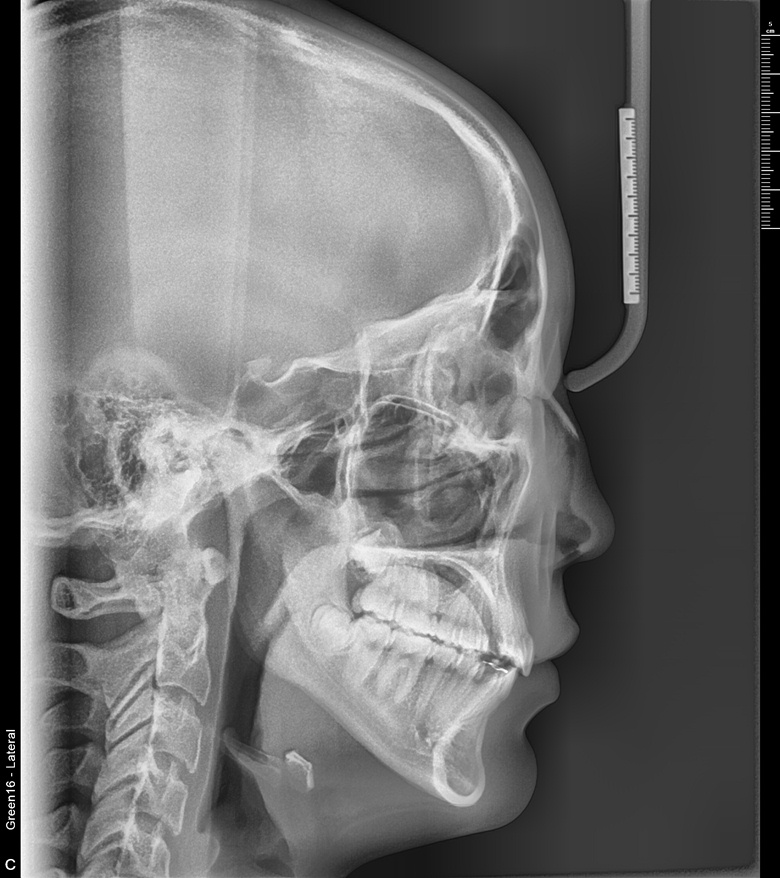

치료 전 사진입니다.